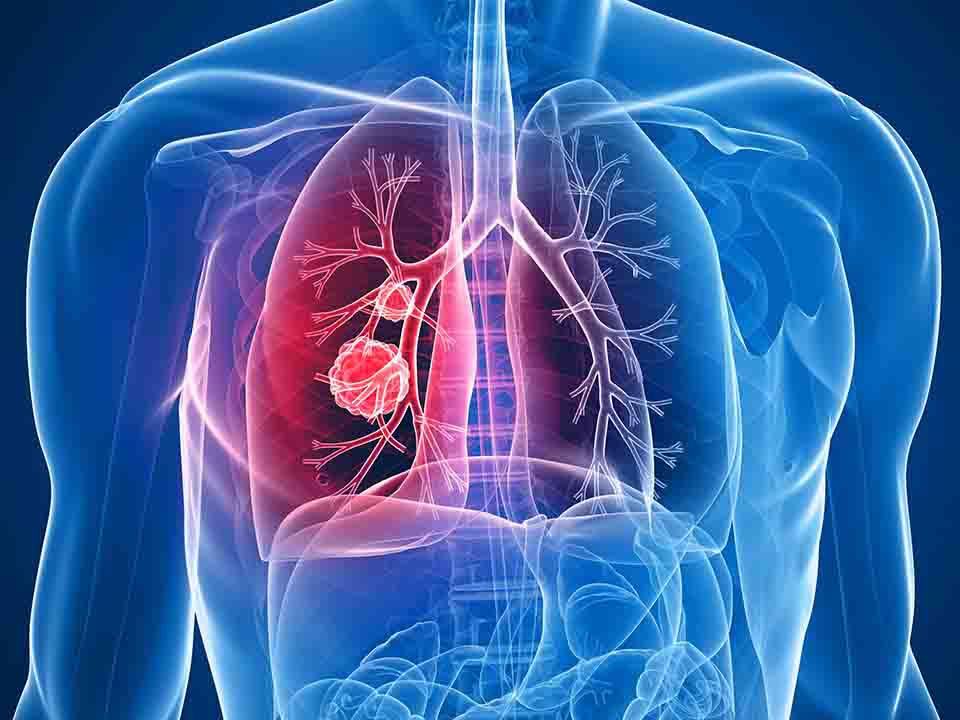

导致肺炎的原因很多,不仅仅有微生物性,还有物理性、化学性等诸多因素。微生物性病因包括细菌性肺炎、立克次体性肺炎、霉菌性肺炎、病毒性肺炎、支原体肺炎等等。而细菌性肺炎中,又可以依据细菌的不同种类进一步划分,如常见的有肺炎球菌性肺炎。那么,肺炎吃什么最好呢? 肺炎患者可选用牛奶,瘦肉,鸡蛋,豆类。少吃辣的,脂肪应限制,多吃蔬菜水果,还可以补充含铁的物质比如动物的内脏,含铜丰富的物质如动物内脏和蛋黄等。如出现缺氧,呼吸困难,有直肠麻痹和消化道出血应禁忌坚果类食物和高纤维的食物以及生葱,大蒜,洋葱辣椒,多吃水果。 同时,大葱、鸭梨、生姜、杏仁、猪肺等都可以使肺炎及早康复。专家提示:肺炎患者应多喝水,尽量减少与过敏源的接触,同时可以铺助一些食疗来缓解病痛。 通过以上内容的介绍,相信大家对于肺炎吃什么最好已经有了一定的了解。如果您还有其他问题,可以点击在线咨询或到我院详细咨询专家。 肺炎专题: 关于肺炎的信息 肺炎是一种常见的多发的感染性疾病,临床表现主要有发烧、咳嗽、多痰、胸痛等,重症者喘气急促、呼吸困难,可危及生命。因此,治疗肺炎不仅需要到正规的医院治疗,肺炎的护理也很重要。  小儿肺炎要注意什么呢?马上就要到冬季了,天气也变的干燥。正是小孩子容易患上肺炎的季节!家长们一定要注意做好小儿肺炎的护理及预防!多关注小儿肺炎的注意事项很重要!下面我们就来给大家具体的介绍一下小儿肺炎的注意事项。  肺炎是由细菌、病毒等致病微生物侵入肺脏而引起的炎症,因它的症状不太明显,因此需要借助一些检查诊断方法来确诊是否是肺炎。那么,肺炎的检查诊断方法是什么呢?下面我们一起来了解。  随着医疗水平的不断进步,目前关于急性间质性肺炎的检查方法还是不少的。下面就为大家介绍一下急性间质性肺炎的光镜检查。  肺炎是一种可轻可重的疾病,轻微的肺炎在家治疗就可治愈,而严重的肺炎则需要住院治疗。那么,肺炎的治疗方法有哪些呢?下面我们为大家详细介绍,希望能对您有所帮助。  重症肺炎的诊断标准是什么?重症肺炎的发生严重威胁到患者的生命健康,所以患者一定要及早的进行治疗,那么,重症肺炎的诊断标准你知道吗?下面就请专家为大家详细的介绍下重症肺炎的诊断标准。  肺炎是一种多发于老年人的呼吸道炎症,这是因为老年人的身体体质弱。在治疗老年肺炎的同时,做好护理工作可以使疾病更快的康复。那么,老年肺炎的护理方法有哪些呢?下面我们一起来了解。  放射性肺炎是一种较为常见,且治疗难度较高的肺炎症状,在治疗放射性肺炎的过程首先需要重视的就是家庭护理。下面就让我们来了解一下放射性肺炎的家庭护理中需要注意哪些重要事项。  肺炎是指终末气道,肺泡和肺间质的炎症。其症状:发热,呼吸急促,持久干咳,可能有单边胸痛,深呼吸和咳嗽时胸痛,有小量痰或大量痰,可能含有血丝。幼儿患上肺炎,症状常不明显,可能有轻微咳嗽或完全没有咳嗽。那么,肺炎的病因是什么呢?  小儿肺炎是一种临床常见病,可发生在四季。如治疗不彻底,易反复发作,影响孩子发育。要想彻底治疗小儿肺炎,首先应了解小儿肺炎的病因,下面我们将为大家详细介绍。  肺炎患者都知道在进行正规治疗的同时,对于肺炎的护理也是必不可少的,通常的护理方法分为日常生活与饮食习惯护理,下面我们就来介绍一下在进行肺炎的护理时要注意哪些饮食习惯。 |